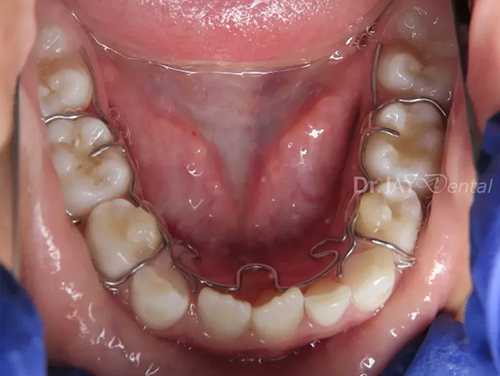

CASE 16

Misaligned teeth , crowding resolving in 3 months , patient still continuing with treatment. Arch expansion and myofunctional therapy

Before

After